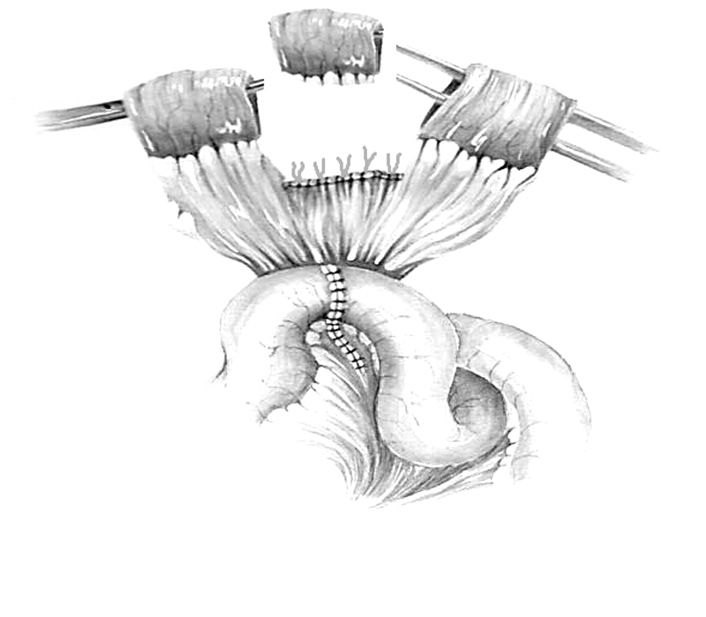

Fig. 4. Two remaining intestinal sections (parts/pieces) are detubularized and stitched together

Fig. 5. The forming of a single tubular ileo transplant from two detubularized intestinal sections

Fig. 6. The final type of ureteroileoureteroanastomosis operation with two reconfigured intestinal transplants according to Yang–Monti in our modification